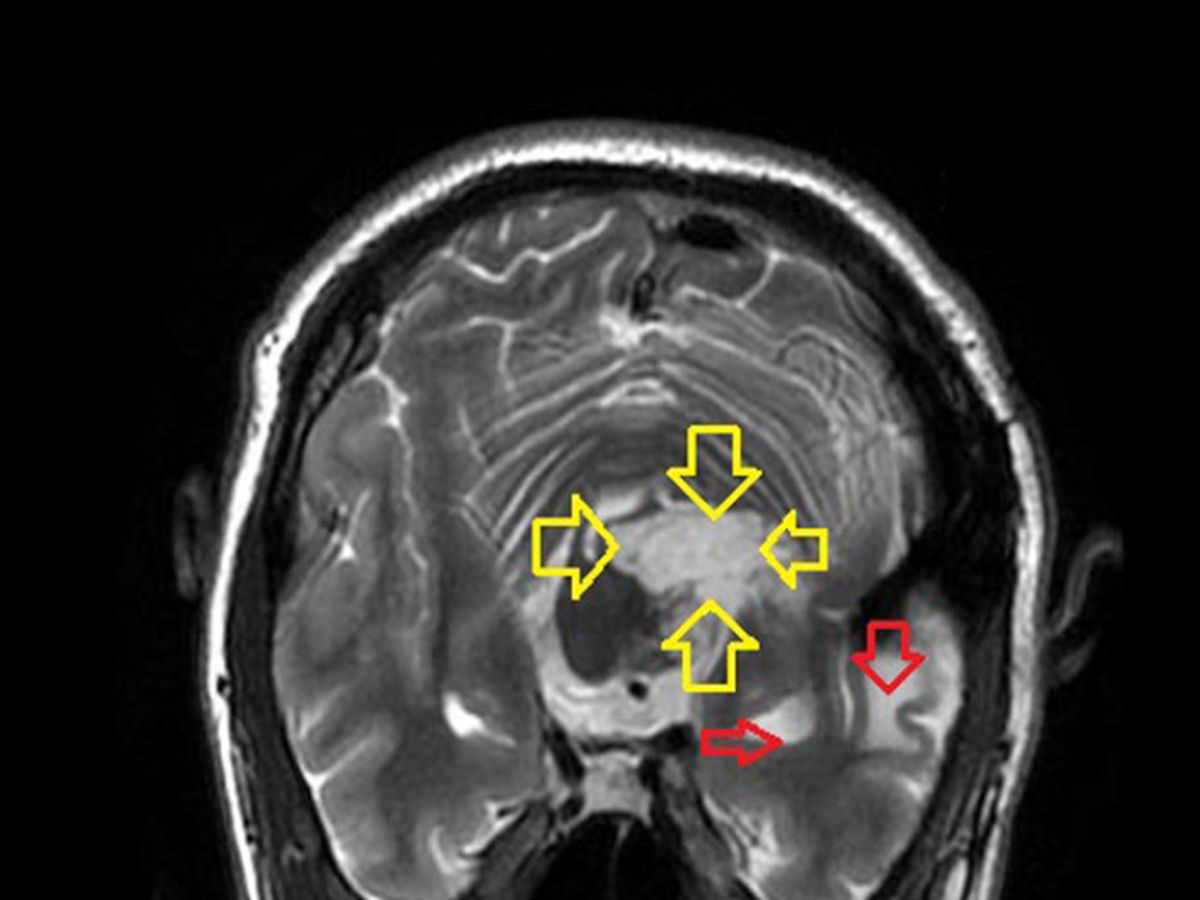

In December of 2008 during my second brain surgery I suffered a stroke, For the last three years I have been riding my bike around Lake Tahoe for charity. With the support of friends and family I have been able to raise over $10,000 for several charities including: The Veterans Community Center, the Capitan Joseph Shultz Foundation, Shriners Hospitals for Children, and the Leukemia and Lymphoma Society. This year on June 4th I plan to ride my bike around Lake Tahoe with my wife and friends in support of Shriners Hospitals for Children and the Epidermoid Brain Tumor Society. If you are interested in sponsorship opportunities or coming along for the ride please contact me. This would not be possible without you. Thank you so much for your contibutions and helping spread the word. Please share. Matt